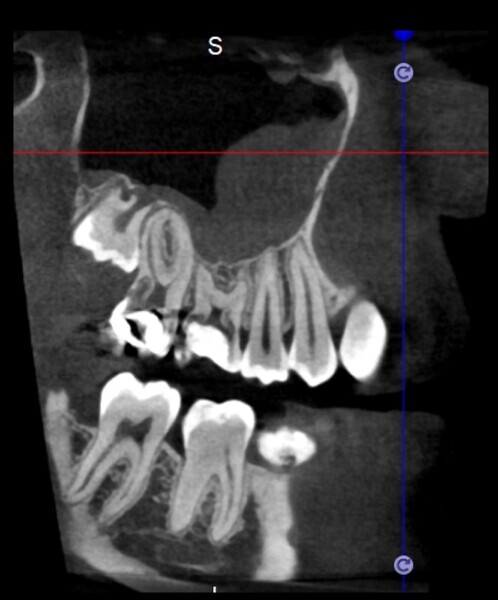

Use of 3D technology in the diagnosis and treatment of endodontic disease